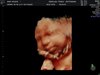

Hej dziewczyny dzisiaj byłam na ostatnim usg 4d przed porodem

Moja.Natalia waży 2080g w skończonym 34tygodniu szacowana waga przy porodzie to koło 3100g. [emoji307]

To ostatnie zdjęcia przed porodem następne będzie już jak będzie na świecie [emoji307] [emoji5]

IMG_20180728_1_21.jpg

IMG_20180728_1_8.jpg